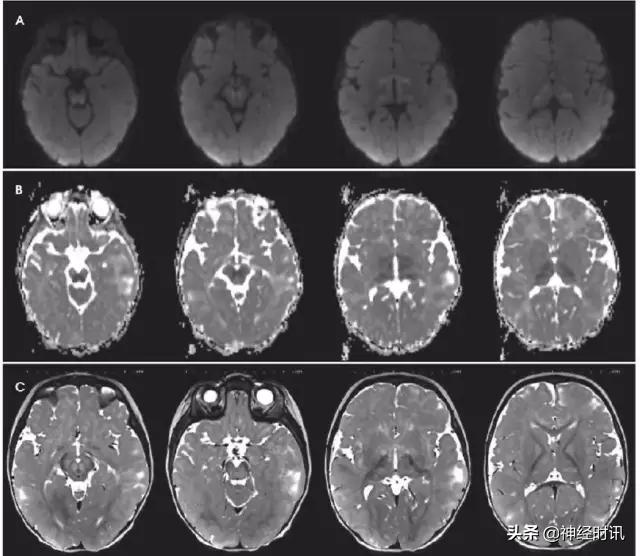

克雅氏病(CJD)是由于朊蛋白错误折叠导致的快速进展性、传染性、致死性神经退行性疾病。DWI比FLAIR或T2WI更加敏感,并伴ADC降低。CJD患者有对称性基底节受累和对称性或非对称性皮层受累(图10)。

图10 一例48岁女性,精神状态改变、亚急性记忆减退伴步态异常1年,近期出现人格改变。MRI显示双侧基底节、丘脑、皮质弥散受限(A:DWI,B:ADC)和T2-FLAIR(C)高信号。患者被诊断为CJD。